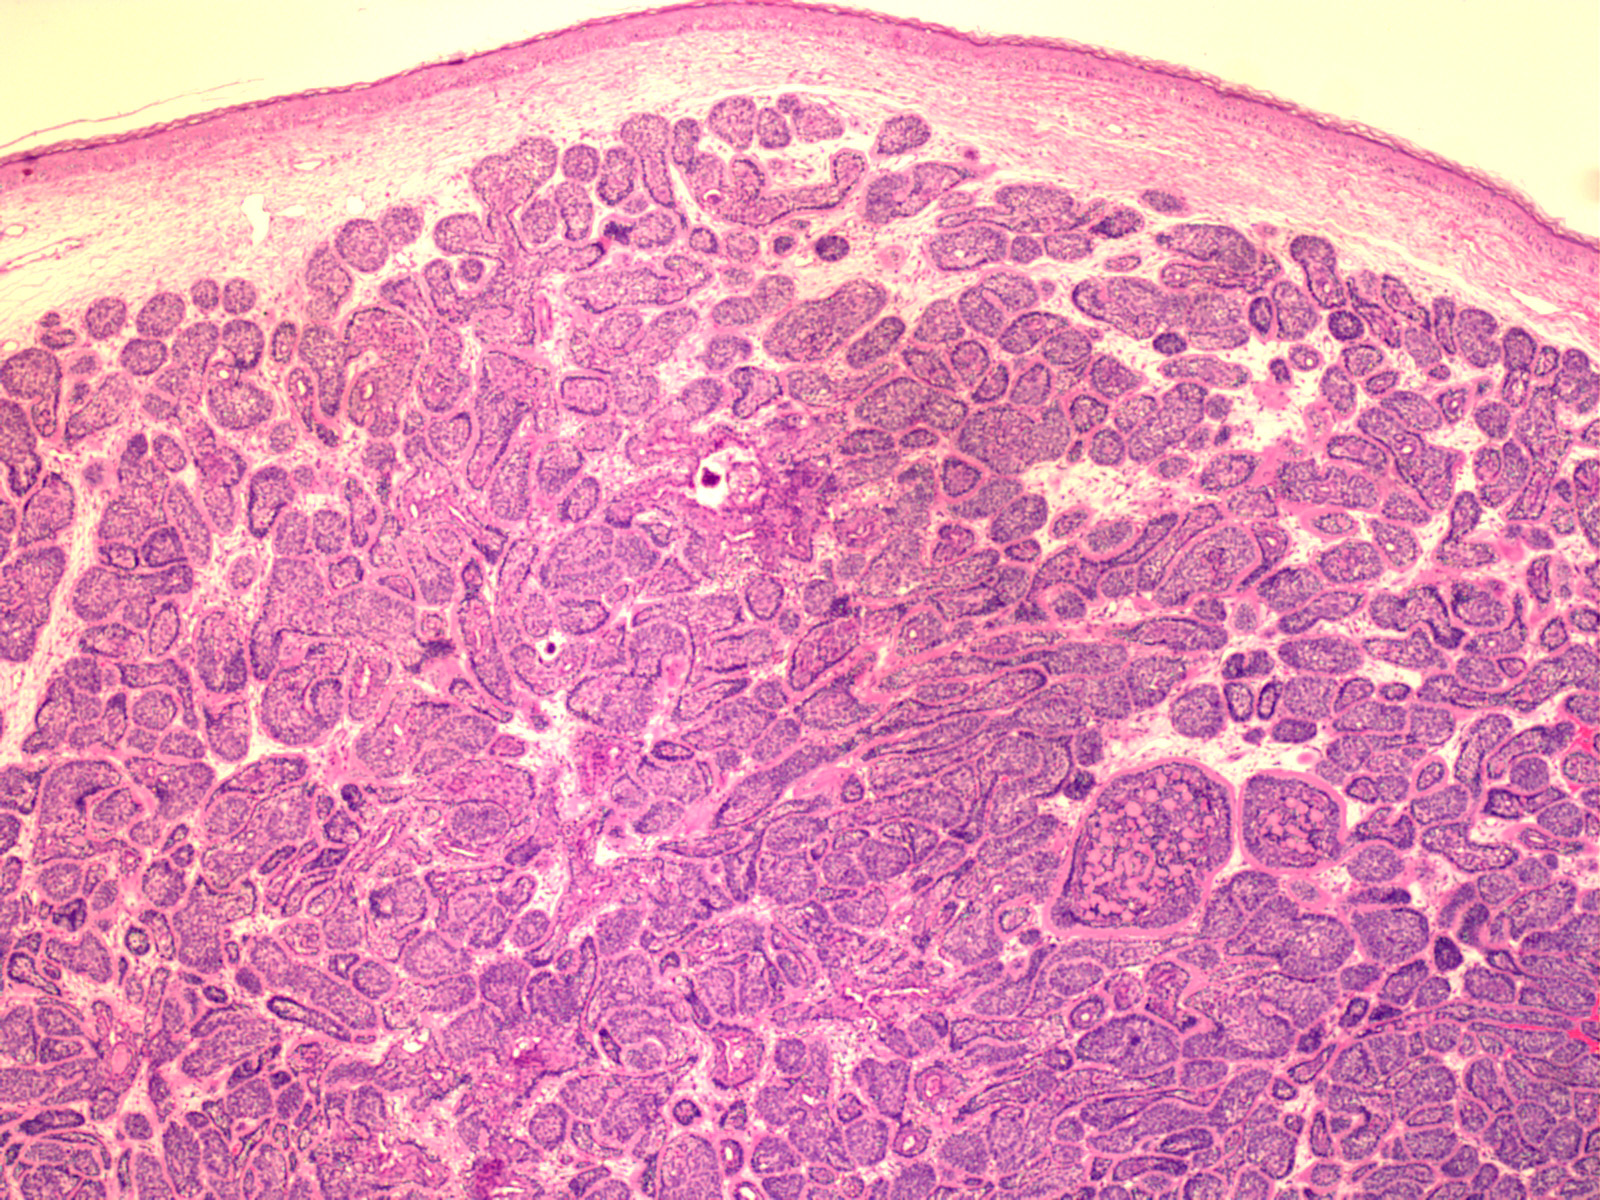

Cylindroma =الأسطوانوم

OLYMPUS DIGITAL CAMERA